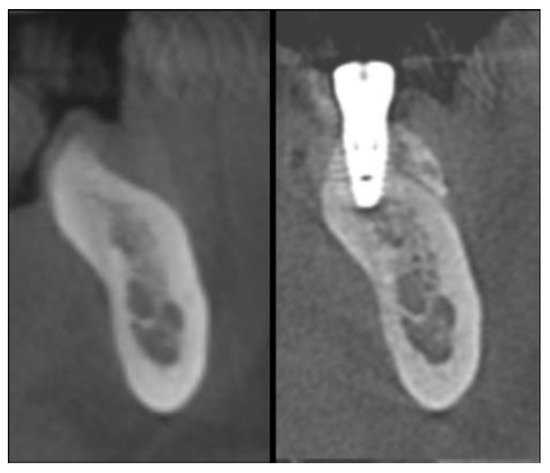

2.5. Re-Entry Surgery and Prosthetic Phases

2.8. Radiographic Assessment